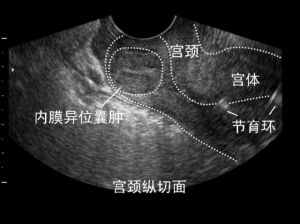

宮頸縱切面納氏囊腫是育齡期婦女常見病,多由於宮頸因分娩、流產及手術損傷或局部經長期刺激感染細菌所致,也可由急性宮頸炎轉變而來。宮頸瀦留囊腫與宮頸癌的發病有一定關係,宮頸腺體囊腫是宮頸慢性炎症時,使腺管及其周圍組織增生並擠壓、堵塞腺口,使腺體分泌物瀦留於內導致腺腔擴張,形成大小不等的囊性腫物而成。

治療子宮頸腺體囊腫並不難,一般先要檢查清楚哪一種病菌感染引起了宮頸炎,檢查清楚後針對感染病菌進行相應的治療。對於不易消退的囊腫,可以先將其刺破,之後再用雷射、冷凍等方法將其燒掉。“納囊”全稱為納博特囊腫,即子宮頸腺體囊腫或子宮頸囊腫,子宮頸腺體囊腫是慢性宮頸炎的症狀之一,主要是因為子宮頸腺的腺管口阻塞,於是腺體的分泌物不能很好地排出,而是瀦留在腺體內,形成囊腫。醫生檢查時可看到宮頸表面有突出的小囊泡。